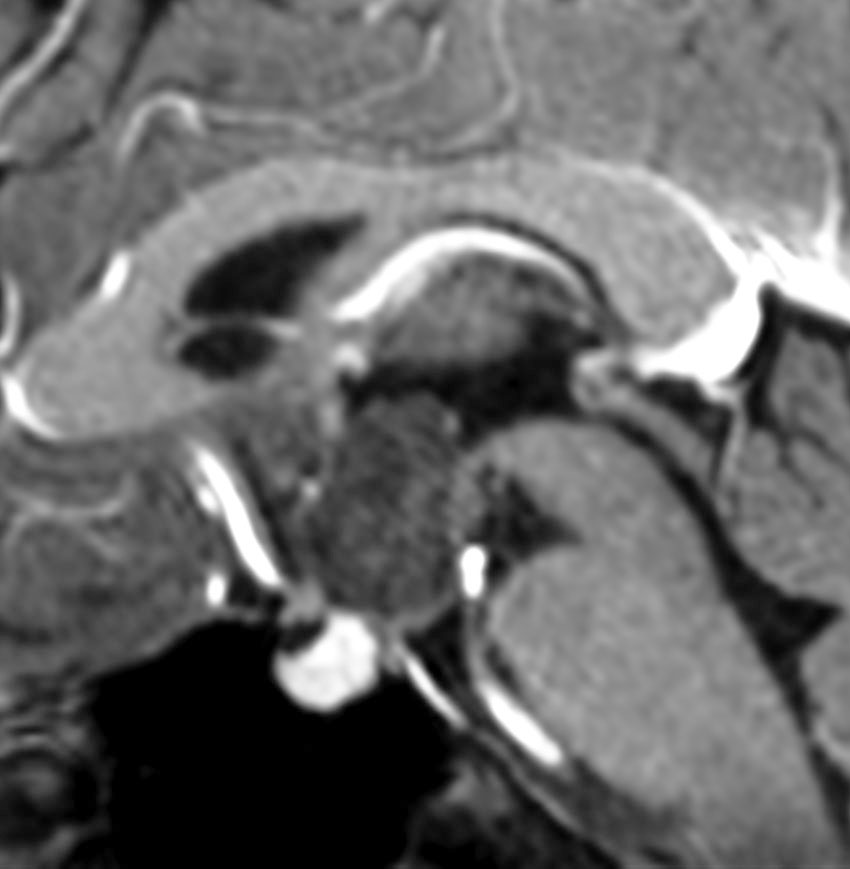

40代になり偶然発見されたものです。視野検査では軽度の右同名半盲がありましたが,本人は自覚していませんでした。おそらく幼小児期から存在したものです。

鞍上槽に強い石灰化を伴う腫瘍があります。視交叉左側から左視索が腫瘍化した,視路毛様細胞性星細胞腫です。右側のガドリニウム増強では一部に増強所見がみられます。施設によっては,頭蓋咽頭腫と間違えられ生検術をされるかもしれません。経過観察のみをします。

左が2016年,右が2023年のものです。7年間で全く腫瘍サイズに変化はありません。小さな腫瘍のう胞も石灰化も不変でした。